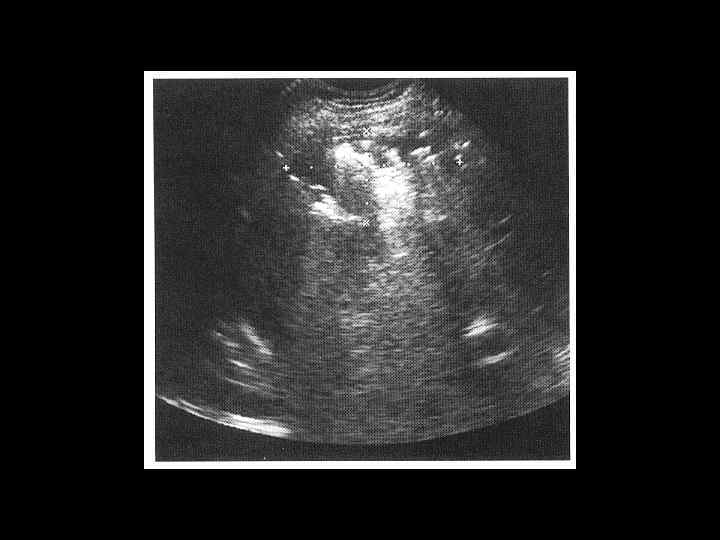

Тот же пациент